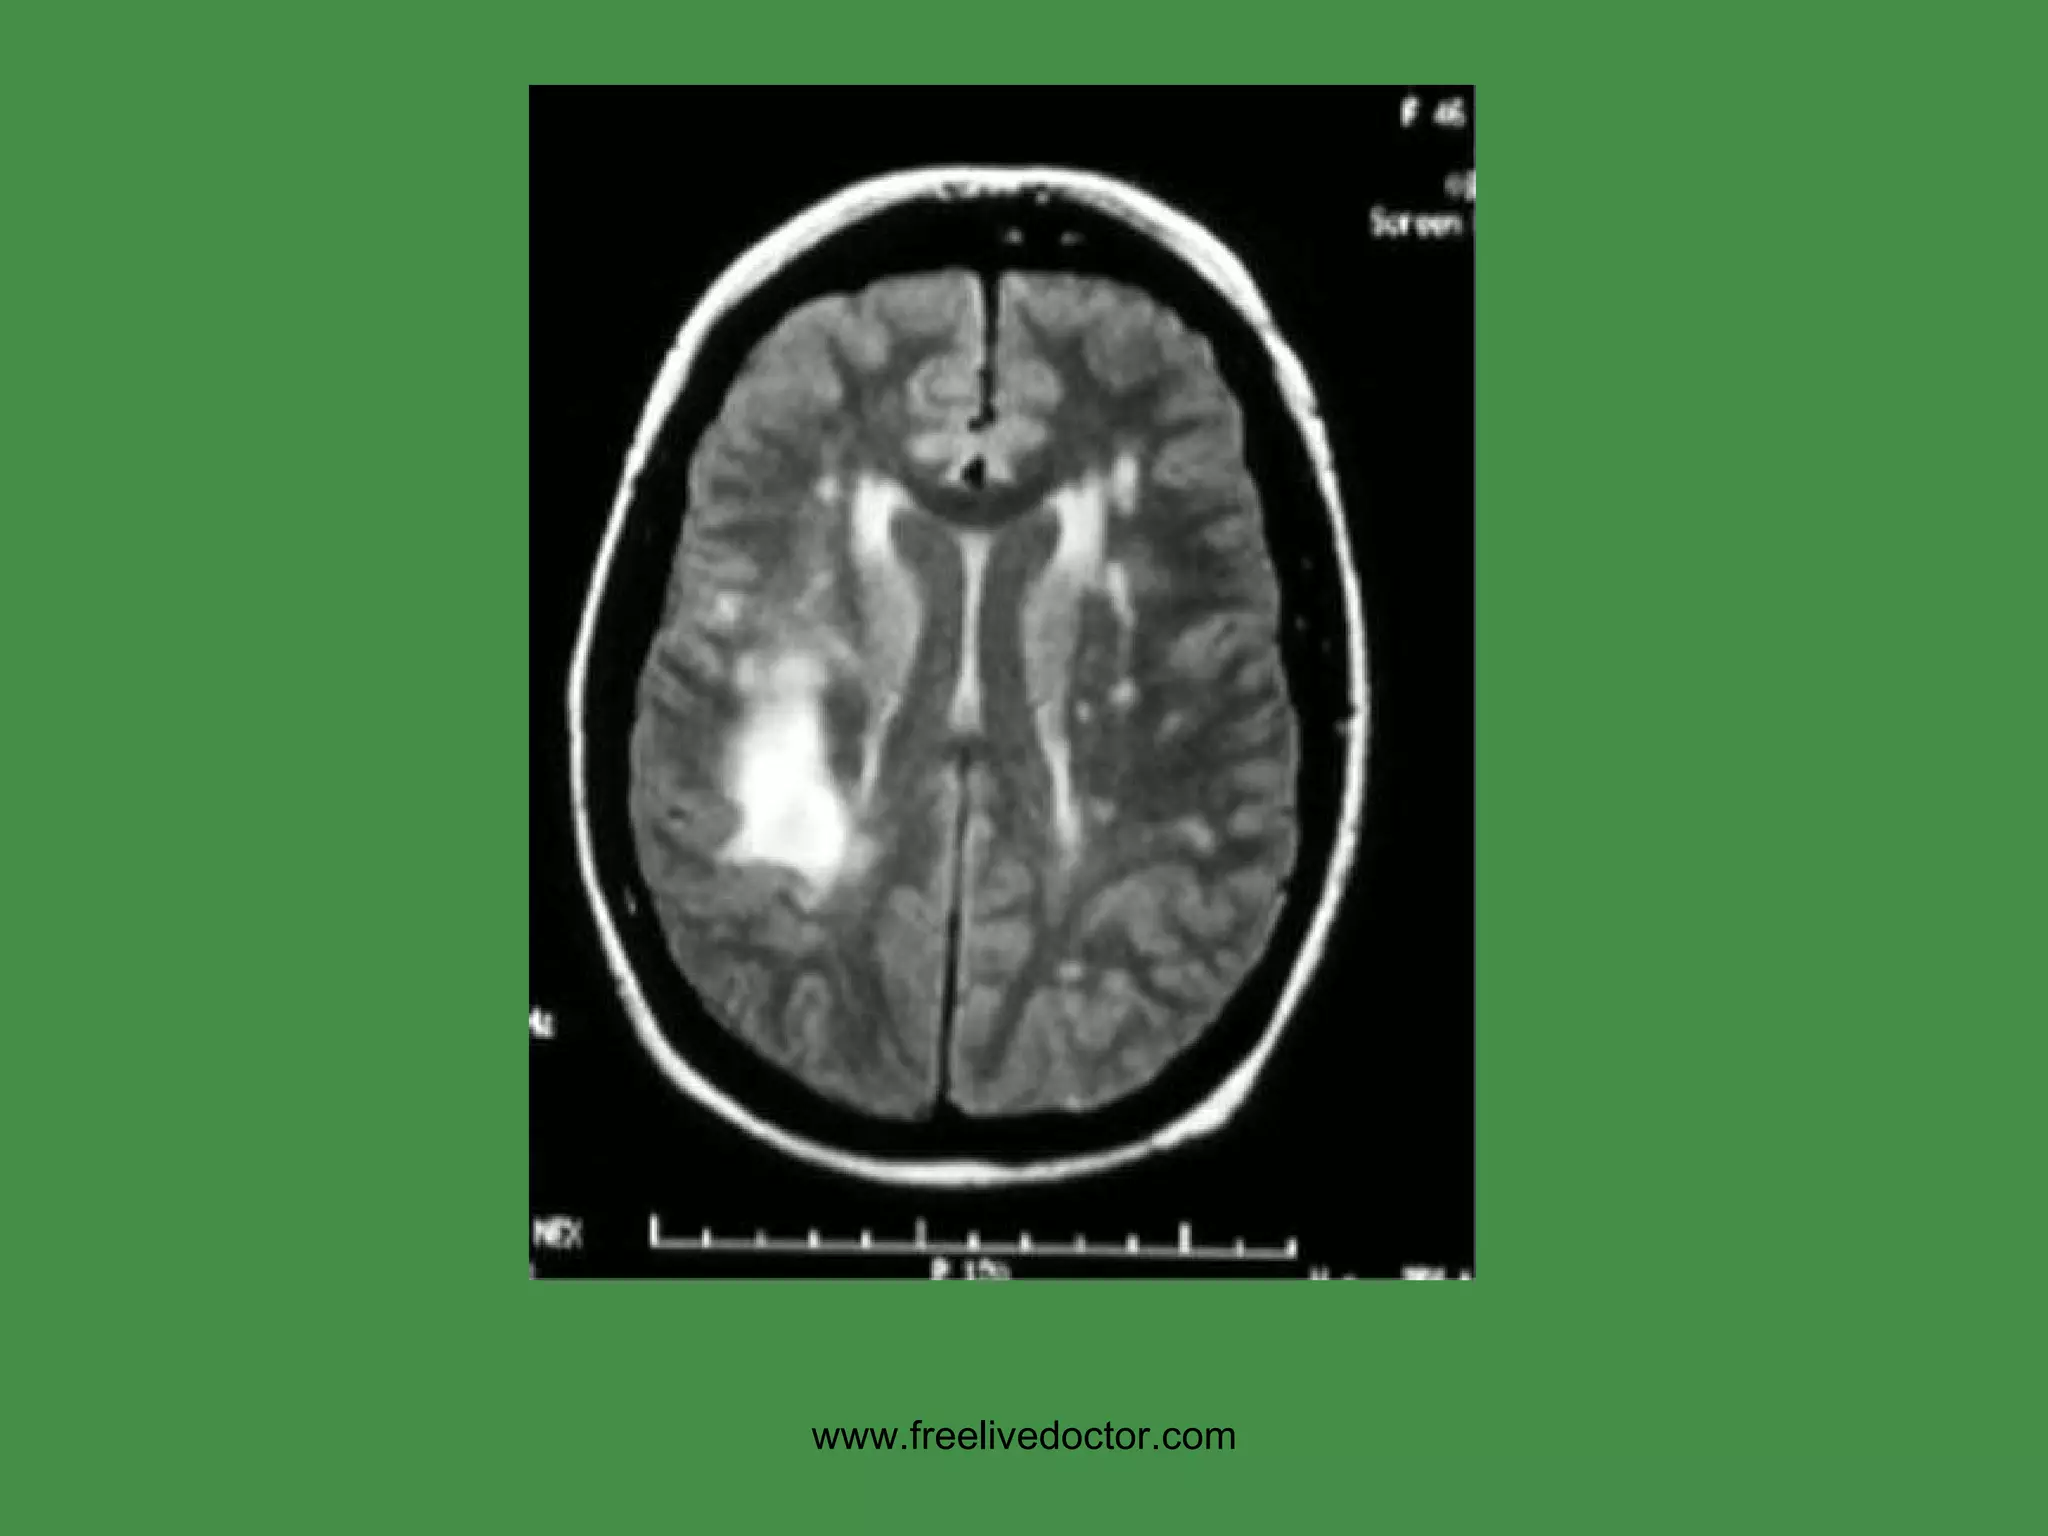

MS Cause:  ? USA prevalence:  1:1000  F>>M,  Ages: 30’s, 40’s Immune response primarily against CNS myelin (white matter) Regional area of white matter demyelination is called “PLAQUE” Increased CSF gamma globulin, i.e., oligoclonal bands Often presents with VISUAL problems EXACERBATIONS/REMISSIONS www.freelivedoctor.com

PLAQUES, MS www.freelivedoctor.com

• #91 Demyelination is associated with gliosis and edema, therefore bright signals on T2 weighted images

• #105 Demyelination, generically, is a NON-specific pattern of CNS reaction to injury of many types and usually goes hand in hand with edema and gliosis, If it wasn’t for the “edema” associated with demyelination, the “plaques” would not be seen on MRI.

• #106 The PLAQUE of MS is NOT like a plaque of skin diseases, i.e., it is not a raised lesion, but an area of demyelination.

• #107 MS gave MRI its first HUGE boom, by virtue of being able to detect these lesions, due to edema!